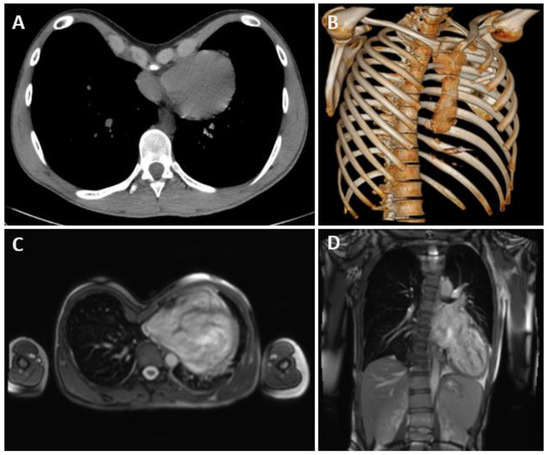

| Case | Age (yr) | HI | Heart Disease | Implantable Medical Devices | ASA | Comorbidities |

|---|---|---|---|---|---|---|

| 1 | 16 | 5 | VF arrest | S-ICD | 3 | - |

| 2 | 15 | 6.8 | MVP | - | 3 | MS, Scoliosis, PA |

| 3 | 21 | 5 | II° AVB | MLP | 3 | ADHD, BD, Asthma |

| 4 | 52 | 4 | Pericarditis | - | 3 | Mondor Syndrome |

| Case | Pectus Technique | Operation Time (min) | Number of Bars Placed | Resection of Costal Cartilage | Wedge Resection of the Sternal Body | Postoperative Complications | Chest Tube Duration (Days) | LOS (Days) |

|---|---|---|---|---|---|---|---|---|

| 1 | Nuss | 80 | 2 | - | - | - | 3 | 28 |

| 2 | Nuss | 455 | 3 | - | - | PAL, fever | 29 | 36 |

| 3 | Nuss | 55 | 1 | - | - | Transitory fever | 4 | 4 |

| 4 | Modified Ravitch + Nuss | 105 | 1 | 6th, 7th, and 8th ribs bilaterally | Yes | AF, Atelectasis | 9 | 11 |